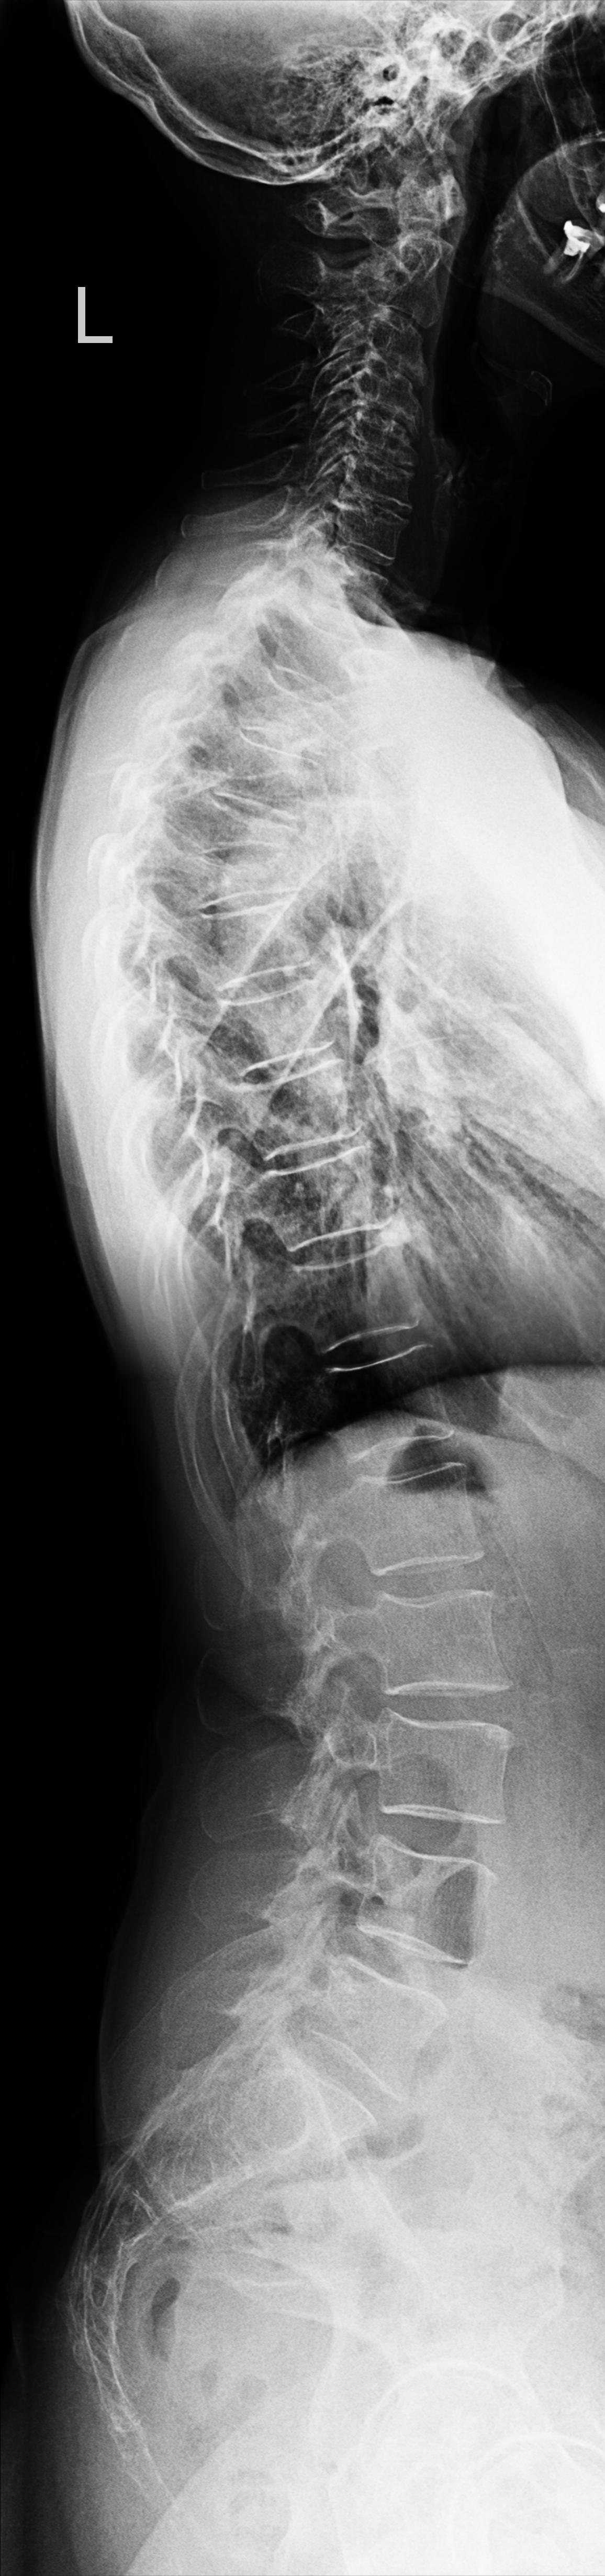

Wirbelsäule Ganzaufnahme lateral

Technik

• FDA: 3 m

• Ausgangsformat: 3 x 35/43

Indikation

Beurteilung der Wirbelsäulestatik, Kyphose und Skoliose.

Lagerung

Mit der Seite am Rasterwandstativ

Kopf in Neutralstellung

Arme nach vorne ausstrecken

Händen kreuzen damit die Schulterblätter rausgezogen werden

Zentralstrahl

Senkrecht auf Wirbelsäule

Einblendung

von Oberlippe bis einschließlich Hüftköpfe

Qualitätskriterien

HWS-BWS-LWS mit Sakrum sollte vollständig und gut beurteilbar abgebildet sein.

Anmerkung

Spezialstativ mit Raster oder Digitalaufnahme mit Abbildung eines Rasters zur Vermessung. Evtl Ausgleichschuhe ausziehen und auch ggf. Verlaufsfilter für guten Kontrast verwenden.